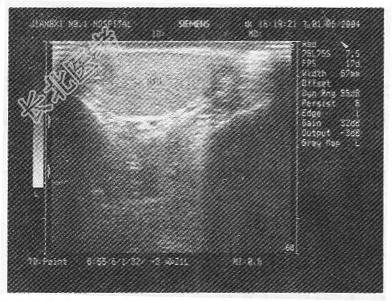

- 单项选择题某患者,阴囊碰伤5日, 现感左侧阴囊不适,超声检查如图所示, 最可能的诊断是

A、睾丸内血肿

B、精原细胞瘤

C、急性睾丸炎

D、睾丸扭转

E、睾丸脓肿